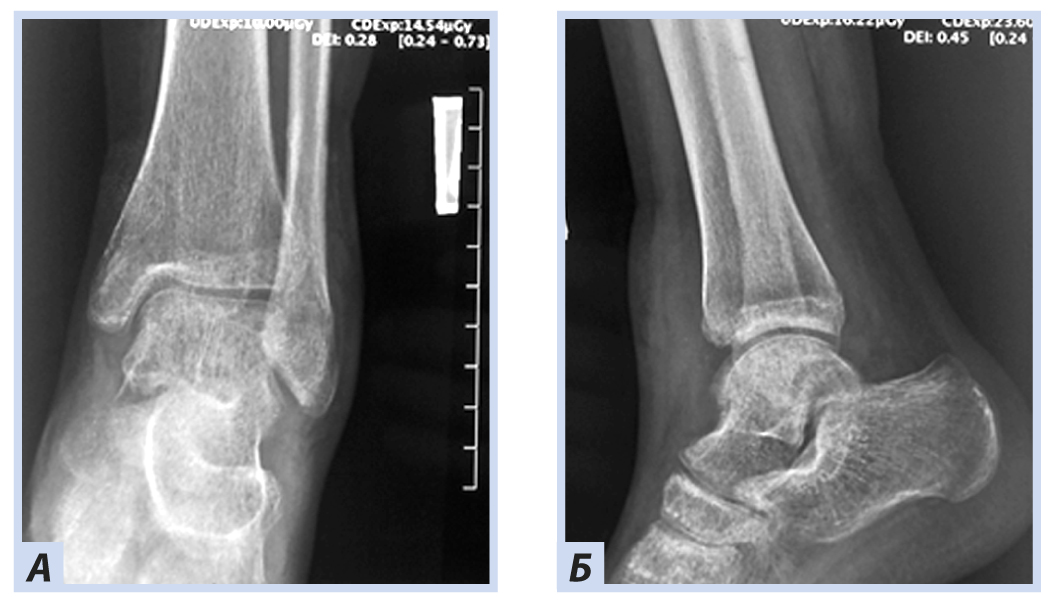

Девочка, 10 лет, диагноз: «Закрытый дистальный остеоэпифизеолиз правой большеберцовой кости, Salter–Harris, II тип». Травму получила, упав с самоката, вследствие чрезмерного сгибания стопы кзади. По механизму травмы — ротационно-флексионный перелом дистального отдела костей голени. По данным компьютерной томографии выявлена значительная степень (5 мм) смещения отломков. Учитывая возраст больной, остеосинтез выполнен закрыто перекрещивающимися спицами. Дополнительная иммобилизация осуществлялась в задней гипсовой лонгете до коленного сустава. Контрольные рентгенограммы выполняли через 4 и 6 нед. после репозиции. Спицы удалены через 6 нед., конфигурация сустава восстановлена полностью (рис. 1–5).

Рис. 1. Девочка, 10 лет. Рентгенограммы дистального отдела костей правой голени. Дистальный остеоэпифизеолиз правой большеберцовой кости, Salter–Harris II тип: А — прямая проекция; Б — боковая проекция.